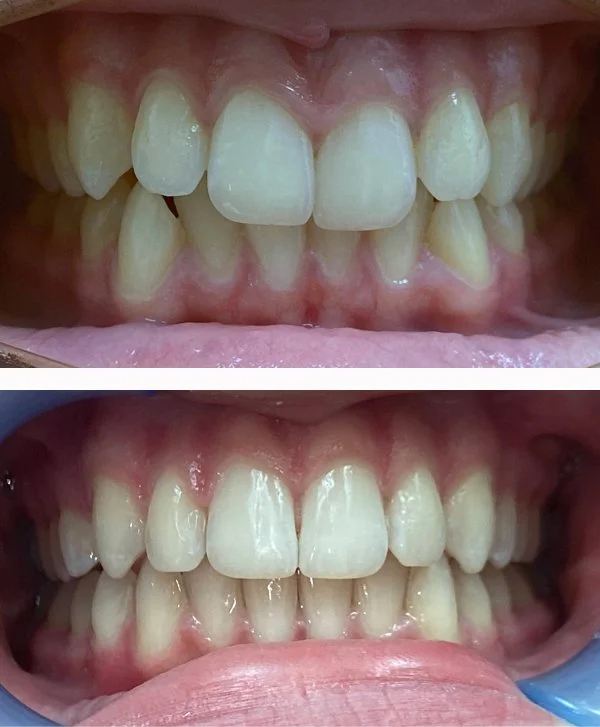

Orthodontics

Movement of teeth to improve function and appearance with Invisalign

Invisalign

Before and after appliance

Orthodontic Appliance